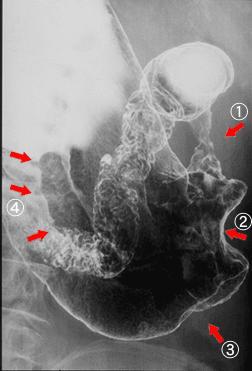

"Linfoma Maligno Precoz" central al antro, que mostró formación similar a Cáncer Avanzado de Estómago

Tokyo Pref., Centro Nacional de curaciones de Cáncer, Hospital Central y Centro Kyusyu de Curaciones de Cáncerc

Tumor Maligno del Sistema Linfático/Linfoma Maligno

estómago(región)/mas de dos

Rayos X

40 -

sm